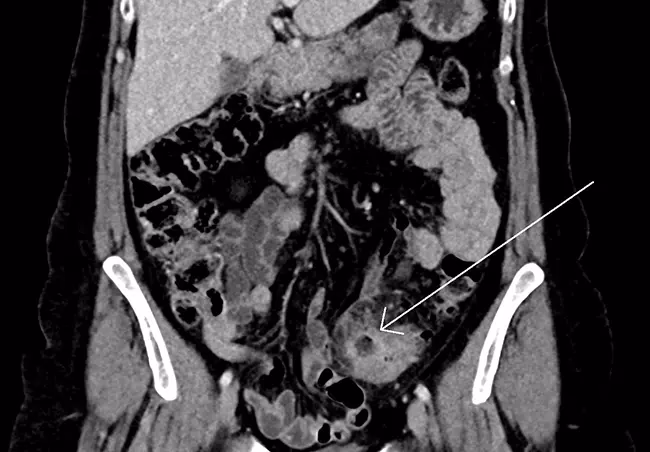

- Komplikationer: Betændelsen kan have udviklet sig til en byld (abscess) eller en perforation (hul på tarmen). Disse tilstande kræver ofte mere end blot antibiotika, f.eks. drænage af bylden eller en akut operation.